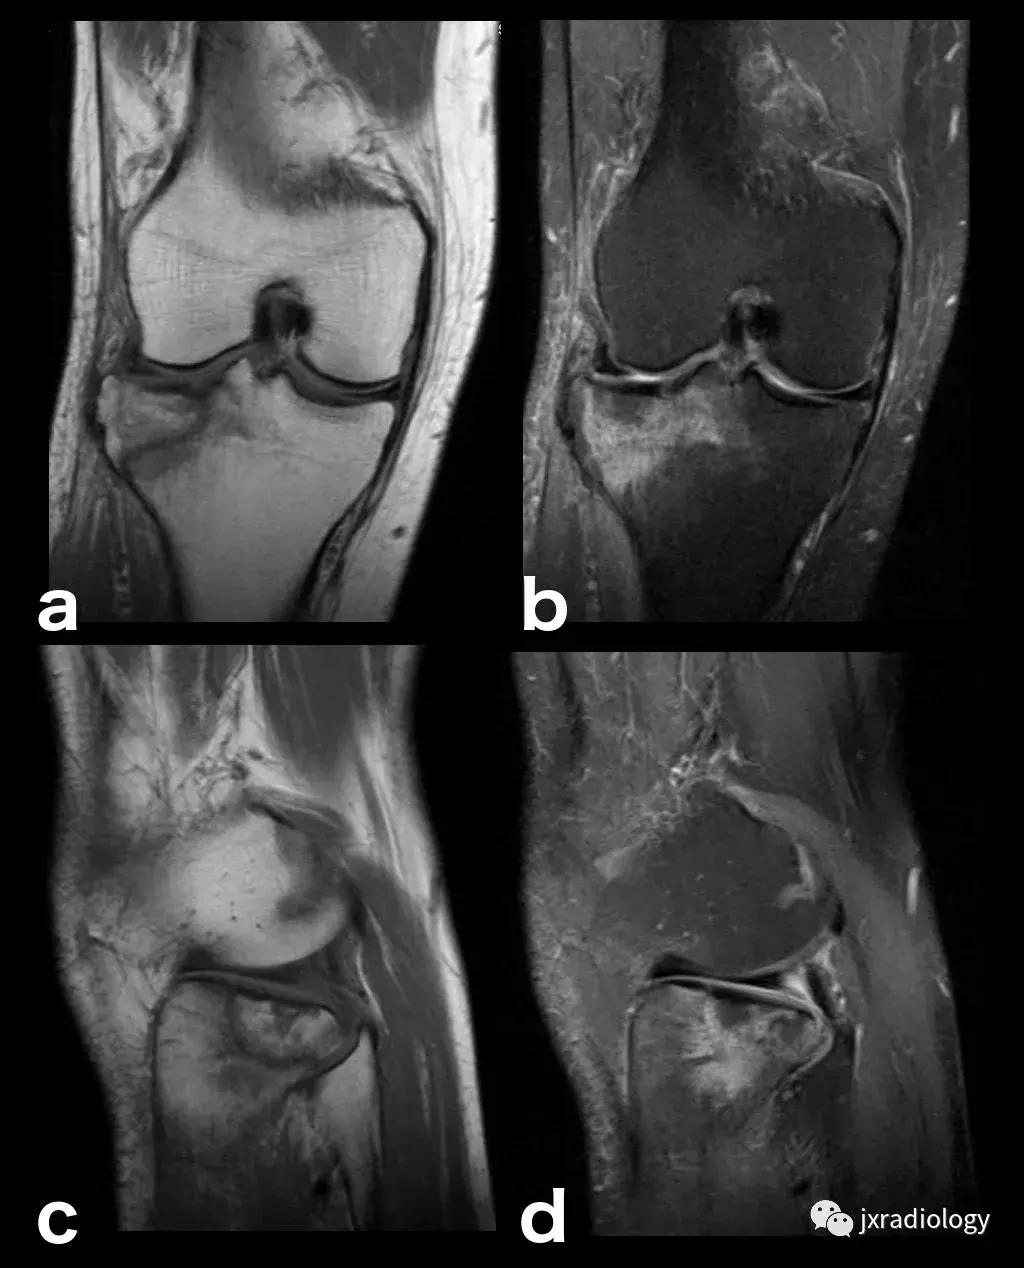

图2:骨性关节炎(OA):男,58岁,股骨内侧髁负重区有软骨缺损,伴有边缘小骨赘和继发性软骨下骨髓水肿。 骨性关节炎通常不与创伤性病因分类,而是作为退行性病变分类(a:冠状T1-WI; b:冠状PDWI-FS; c:矢状PDWI-FS)。